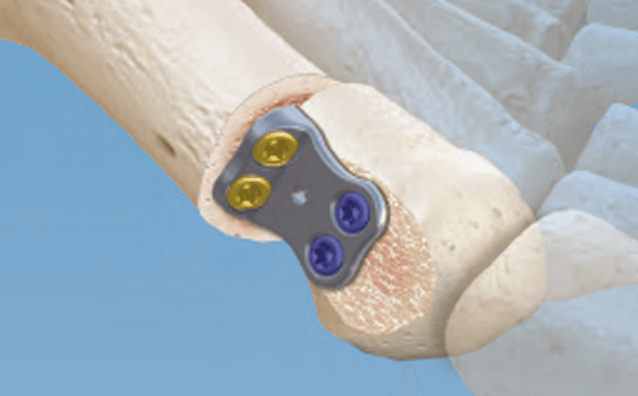

CONMED Foot and Ankle offers tailored innovation and simplified solutions. Explore our complete portfolio of arthroplasty, biologic, fixation, implant, suture anchor, and instrumentation offerings for foot and ankle surgery.

Dr. Early - First MTP Fusion Technique with Metatarsal Head Bone Loss